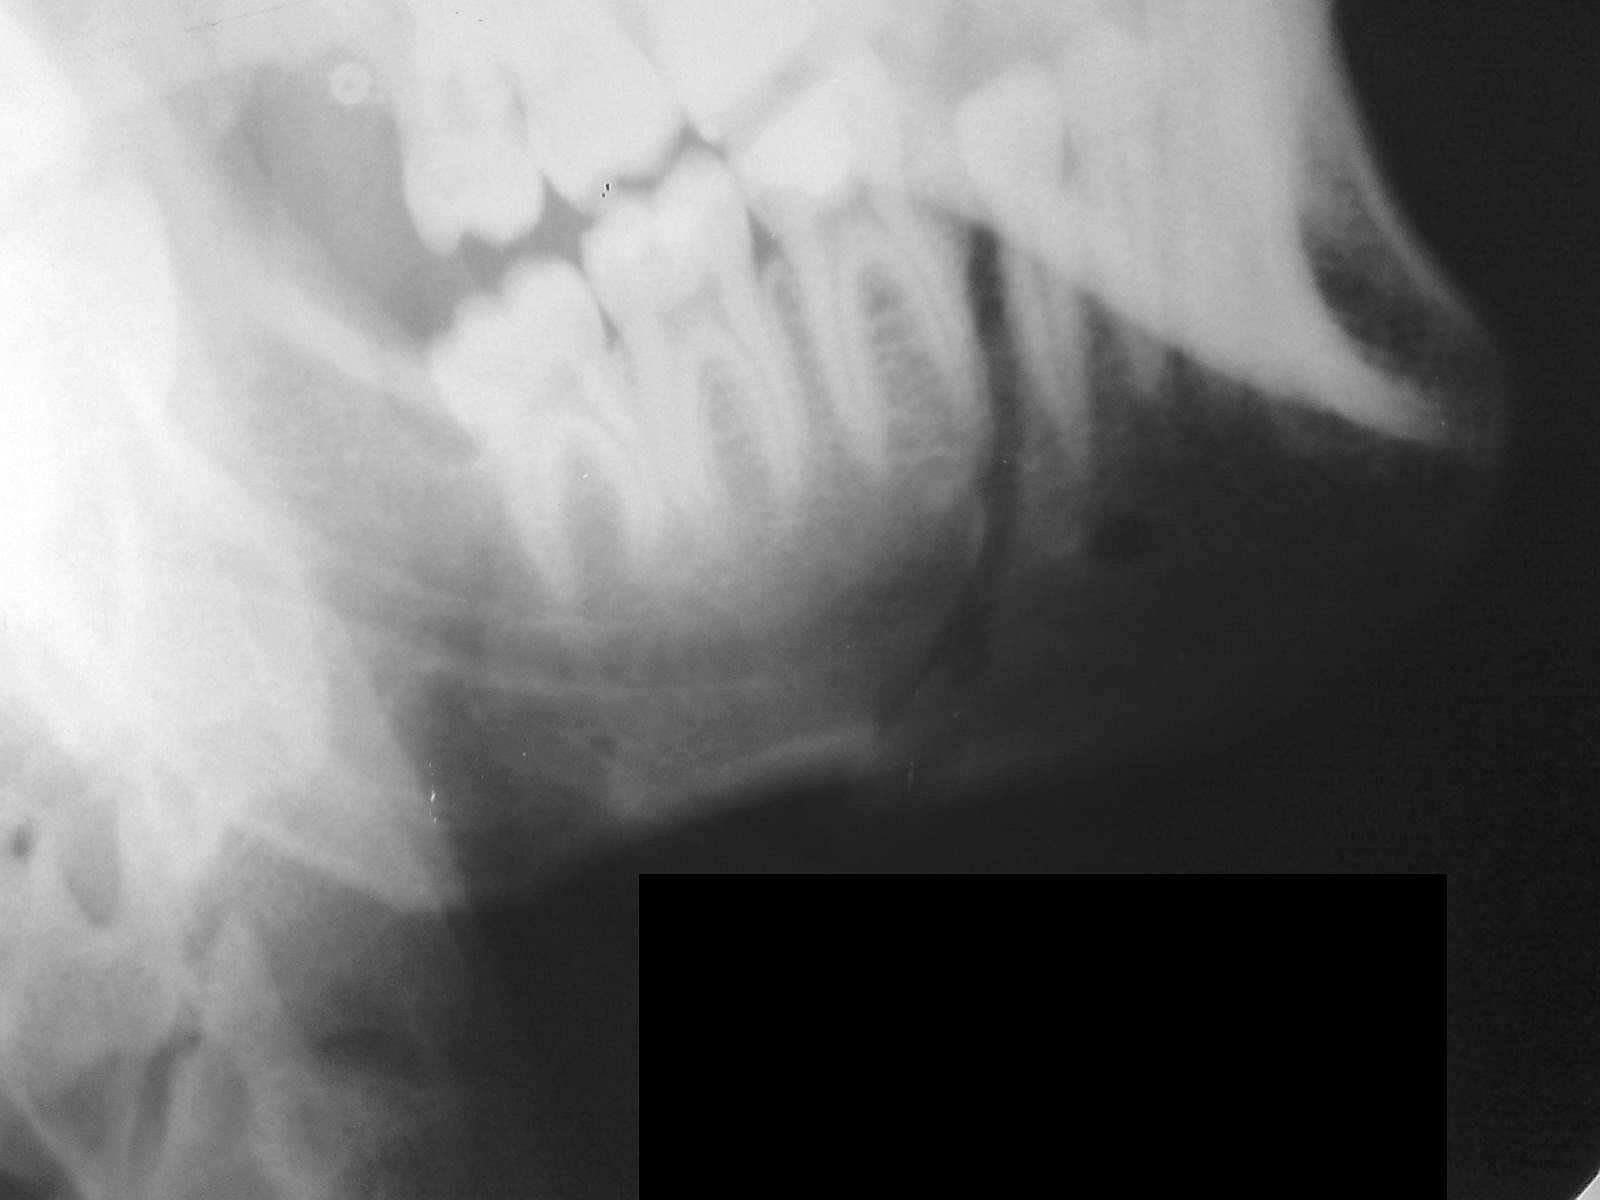

А у нас так ломают челюсти

У этого 3 г. назад нелеченная травма, теперь остеомиелит